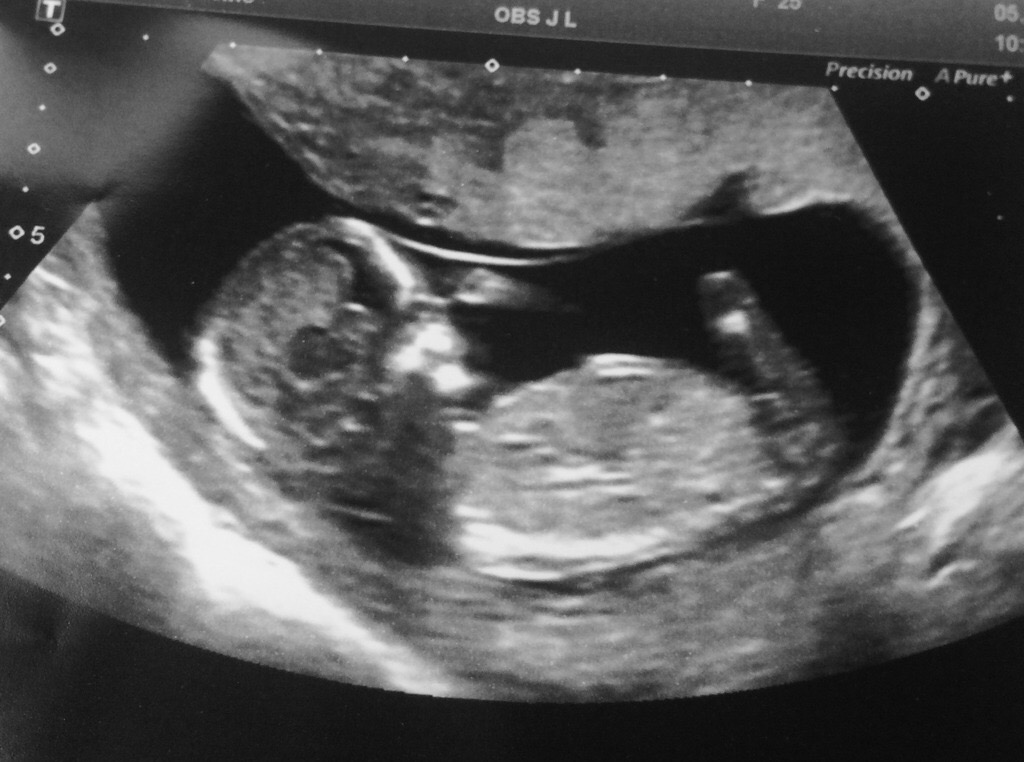

Hi guys! I've been on a few gender prediction forums and posted my scan photo but no one seems to reply 😔 I would love for any of you to put your guesses forward as I love the fun of guessing baby's gender! So here is my scan at 13 weeks, the nub iv been told is hidden. But I would love to hear what you all think as I have to wait until the 24th of October to find out the baby's sex and the suspense is killing me haha!!!

Attachment 33210